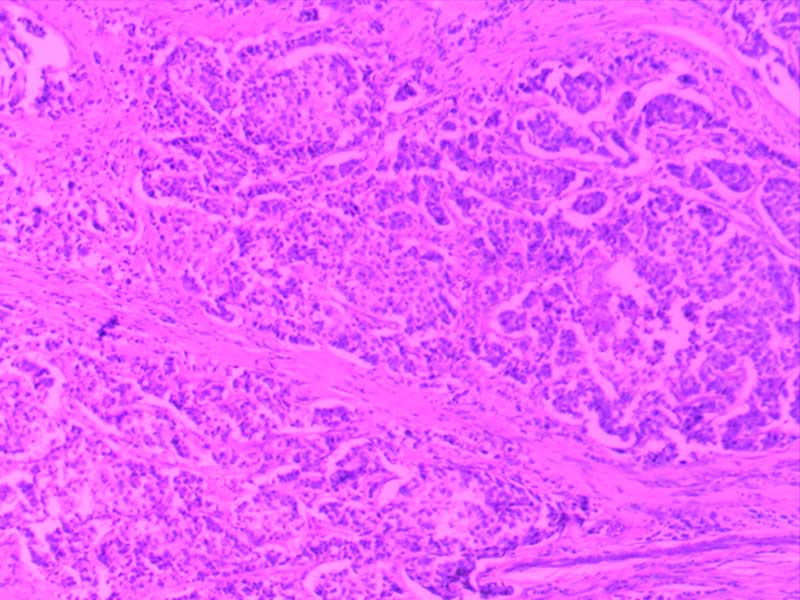

神经鞘瘤-10倍-(2)

神经鞘瘤-10倍

大叶性肺炎(红肝期)10倍

大叶性肺炎(红肝期)-10倍